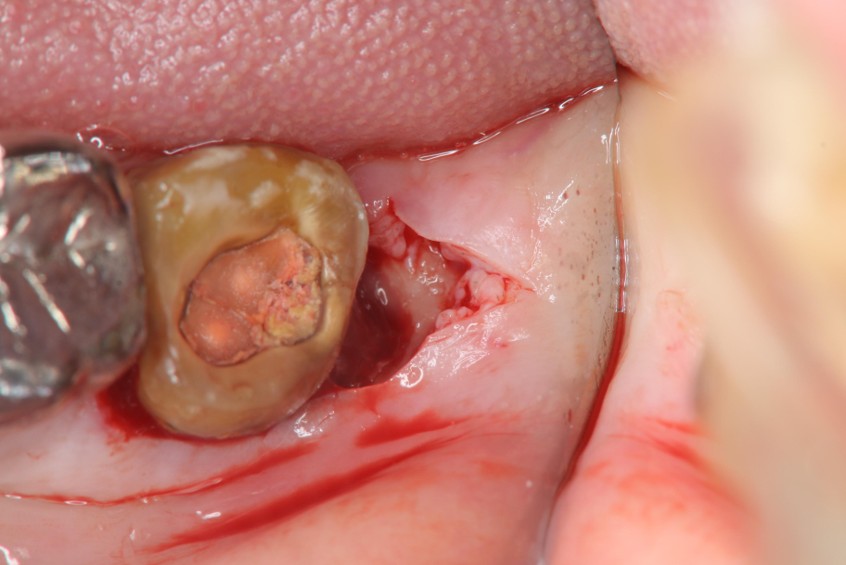

治療前,蛀牙齒質破壞

治療前,患者已接過根管治療

水雷射牙冠增長手術

6週牙齦癒合良好